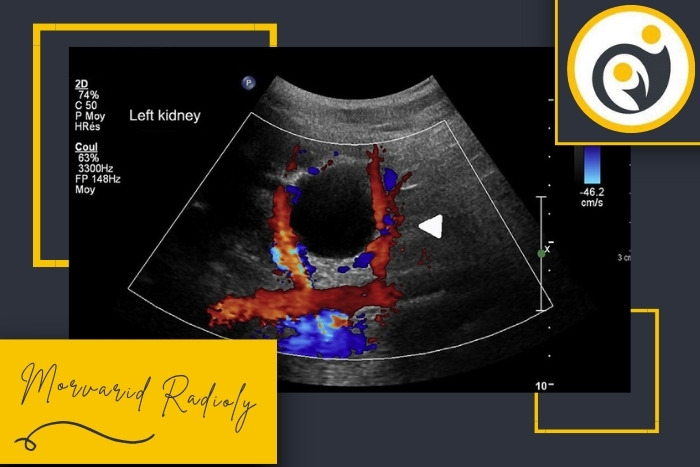

در بررسی داپلر پزشک به جهت و سرعت جریان خون در شریان کلیوی، ورید کلیوی و شاخه‌های کوچک‌تر توجه می‌کند. هرگونه کاهش، انسداد یا برگشت جریان خون می‌تواند نشانه‌ای از تنگی، لخته یا اختلال در عملکرد کلیه باشد. شاخص مقاومت عروقی (RI) نیز از جمله پارامترهای مهمی است که در گزارش ثبت می‌شود و تغییرات آن می‌تواند نشانه‌ای از رد پیوند یا التهاب باشد.

در تفسیر داپلر پیوند کلیه چند محور اصلی بررسی می‌شود. هدف این است که وضعیت خون‌رسانی، خروج خون از کلیه و پیامدهای فشاری یا التهابی مشخص شود.

RI بسیار بالا با کاهش شدید جریان دیاستولیک یا برگشت دیاستول

حالت هشدار دهنده است. در ترومبوز وریدی یا فشار خارج‌کلیوی شدید دیده می‌شود و نیاز به اقدام سریع دارد.

عدم مشاهده جریان در ورید کلیوی یا طیف غیرطبیعی

مطرح‌کننده ترومبوز وریدی است. کاهش شدید دیاستول در شریان‌های داخل کلیه آن را تقویت می‌کند.